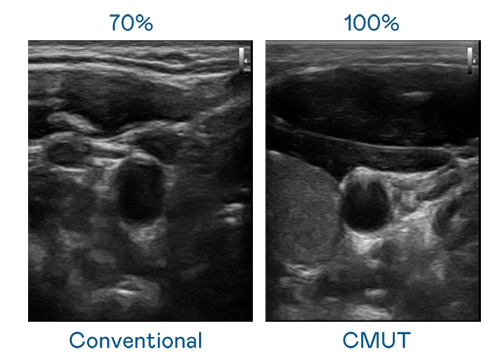

CMUT 技術是一種用電容式微機電元件來產生超音波訊號的技術。與傳統 PZT 壓電式技術相比,CMUT 頻寬增加 30%,更寬頻的超音波訊號讓影像解析度大幅提升,是實現高影像品質醫療超音波掃描、促進精準醫療發展的關鍵技術。

超音波影像的解析度高低,首先取決於探頭能發出的訊號頻寬。BG真人 CMUT 可提供高清晰的超音波訊號,提供高頻寬、高靈敏度、影像紋理細節更高的超音波影像,協助醫護人員縮短影像判讀時間及利用精準的醫療影像進行診斷。